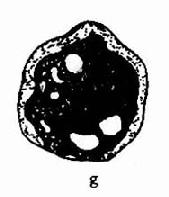

(四)精子形态(见图11-1)

通常用于精子形态学检查的方法的有两种,一种是制成新鲜湿处副县长相差显微镜观察;加一种是将精子固定、染色后用亮视野光学显微镜观察。两处方法检查的精子形态无明显差别,染色后精子头可能稍有缩小。

1.正常精子形态检测政党精子形态的应遵循严格标准:①正常精子头部呈椭圆形,其正常标准为头部长度为4.0-5.5μm,宽为2.5-3.0μm,长与宽的比值为1.5-1.75项体区占头部的40-70%;②必须不存在颈、中段或尾部的缺陷;③细胞质微粒不大于正常头部的1/3;④将所的处于边沿异常状态的清子均列为不正常。

2.有缺陷精子:用这种形态学分析方法考虑的精子细胞功能部位,因此认为没有必要常规的去区分所有头部大小和形态之间可划或尾部缺陷之间的变异如果大多数精子细胞中出现某一种部位的异常,则应对这一普通的缺陷给予注释。需记录的缺陷有:

(1)头部形状、大小缺陷:包括大头、小头、锥形头、梨头、无定形头、空泡样头(头部大于20%区域出现不着色的空泡区、)双头或以上缺陷的联合体。

(2)颈、中段缺陷:包括缺尾可见到游离或脱落的头部,未附着或弯曲尾尾与头部长轴结呈90度角,肿胀、不规则、弯曲的中段,异常薄的中段无线粒体鞘或以上任何类型缺陷的联合体。

(3)尾部异常:包括短尾、多尾、发夹状尾、断尾、宽度不规则或卷尾、或尾部伴有末端微滴,或以上任何类型缺陷的联合体。

(4)细胞质微粒:大于正常头部的面积的1/3。细胞质微粒一般位于颈可中段部分,也有未成熟精子微粒沿尾部分而布在不同部位。

许多形态学的异常的精子有多种缺陷。当多种缺陷同时存在时,只记录一种,但应优先记录头部缺陷,其次为中段缺陷,最后为尾部缺陷。每种精子缺陷的平均数目称为畸形精子指数,是预测精子在体内、体外功能有意义的指标,因此形态学分析应该是多参数原,应分别记录每种缺陷。异常形态见图11-1。

精子形态

图11-1 精子形态

[临床意义] 正常精液中正常形态的精子应≥30%,精液中正常形态的精子减少称畸形精子症,与睾丸、附睾的功能异常密切相关。可见于生殖系感染。精南疆静脉曲张、雄性激素水平异常时;某些化学药物(如硝基唪喃妥英)、遗传因素也可影响睾丸生精功能,导致畸形精子增多。